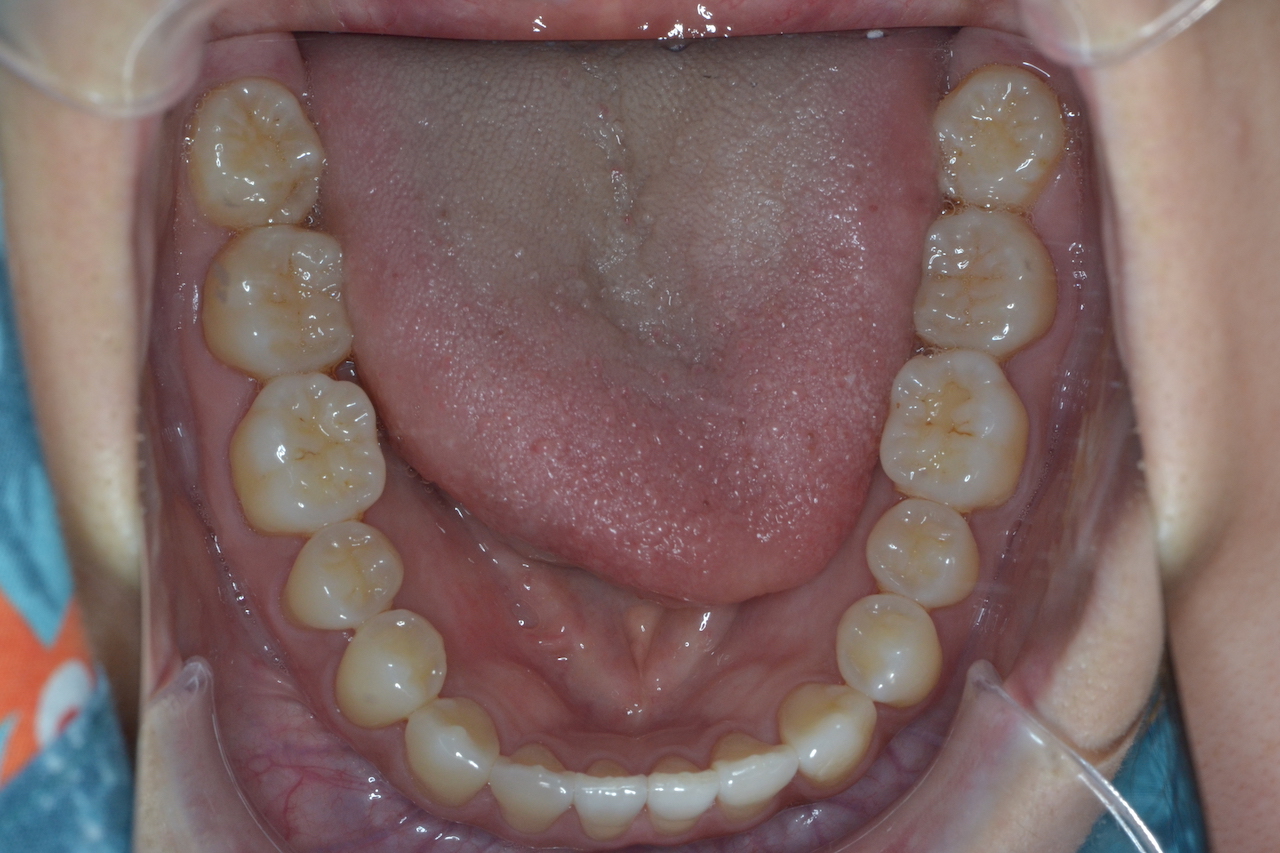

親知らずがきれいに生える人の割合は?生え方の種類や抜歯が必要なケースを紹介初台駅から徒歩1分の歯医者「初台内藤歯科」

親知らずは、前歯から数えて8番目の歯です。 生えてくる時期は、10代後半〜20代前半、人によっては、親知らずが生えてこない場合やそもそも親知らずがない人もいます。親知らずには抜歯すべき場合とそうでない場合がありますが、どちらの場合も一般的にはあまり知られていません。. 親知らずを抜かない3つのメリットとは. 「必要ない歯」「抜いた方がよい歯」というイメージも強い親知らずですが、実は抜かずに残しておいた方が将来歯を失った際に治療で利用できるというメリットがあることは、あまり知られていません。. 具体的に.